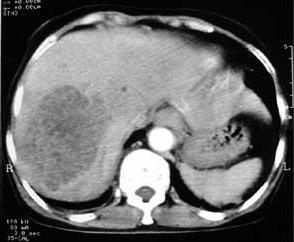

5.頭顱CT 掃描(CT) 臨床表現為腔隙性腦梗死的患者,CT 見有腔隙性梗死灶者占66%~76%。CT 對幕上>5mm 的腔隙病灶易於發現,而對<5mm 或位於腦幹的病灶常難以檢出。Rascal 等報導單純運動性輕偏癱綜合徵者,病後36h 檢查陽性率高達97%。一般病後10 天左右更易出現陽性改變。

(1)非增強掃描:病灶主要位於基底節區、丘腦、內囊、腦幹或放射冠、側腦室旁,呈圓形或橢圓形低密度灶,邊界清楚、直徑2~20mm,占位效應輕,一般僅為相鄰腦室受壓,多無中線結構移位。梗死區密度約於4 周后接近腦脊液密度,並呈現萎縮性改變,即同側側腦室和(或)鄰近腦池、腦溝局限性擴大,中線結構可有輕度的同側移位。

(2)增強掃描:梗死後3 天~1 個月,病灶可呈均勻或斑片狀強化,以2~3周時此效應最為明顯。待病灶密度與腦脊液密度相等時則不再強化。

(3)多發性梗死痴呆的CT 掃描徵象:①腦皮質或皮質下多發的大小不一的低密度梗死灶,主要分布於基底節區及額、顳、枕葉皮質區。②大部分病例可呈腦萎縮改變,即腦室或腦溝擴大,腦皮質、髓質萎縮。③可伴有Binswanger 病(皮質下動脈硬化性白質腦病,SAE)CT 影像特徵:腦室周圍及半卵圓中心白質內的大致對稱性低密度影,呈月暈狀或傘狀,邊緣模糊,多位於側腦室前方或後方。灰/白質密度比值增加。